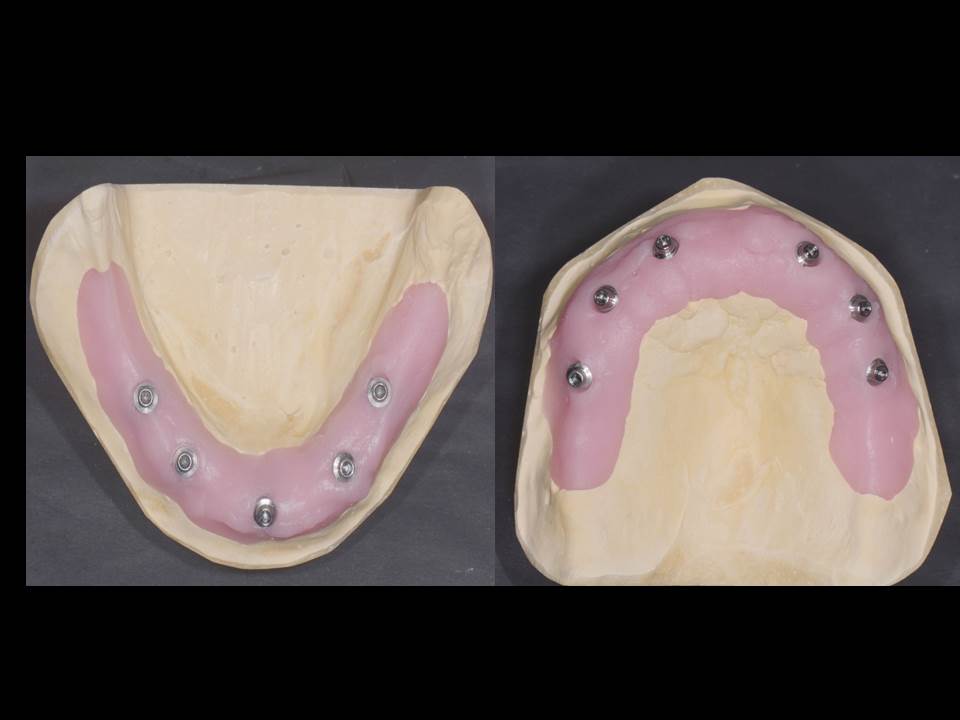

Prótesis fija OT BRIDGE

OT Equator Biologic Abutment